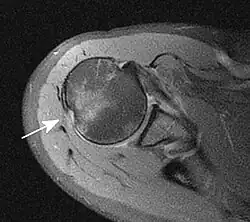

Grundlage ist die Anamnese (Unfallmechanismus) und körperliche Untersuchung (Funktionseinschränkung). Dabei muss insbesondere die Schädigung von Blutgefäßen und Nerven beachtet und dokumentiert werden. Durch Röntgenbilder in verschiedenen Ebenen wird die Diagnose gesichert und eine Fraktur ausgeschlossen. Zum Ausschluss einer Bankart-Läsion (s. u.) kann eine MRT-Aufnahme angefertigt werden.

Als Hill-Sachs-Delle bezeichnet man eine Knochenimpression am Humeruskopf. Sie kann durch eine Unterfütterung mit Spongiosa oder eine Drehosteotomie (nach Weber, nur noch selten angewandt) behandelt werden. Unter einer Bankart-Läsion versteht man den Abriss des knorpeligen Labrum glenoidale inferius von der Gelenkpfanne. Daraus kann eine vordere Schulterinstabilität resultieren. Die operative Therapie besteht in einer arthroskopischen Refixierung (Bankart-repair) oder einer Rekonstruktion mittels eines Knochenspans, z. B. in der Technik nach Latarjet. Beide Läsionen sind Risikofaktoren für ein rezidivierendes Auftreten weiterer Luxationen.